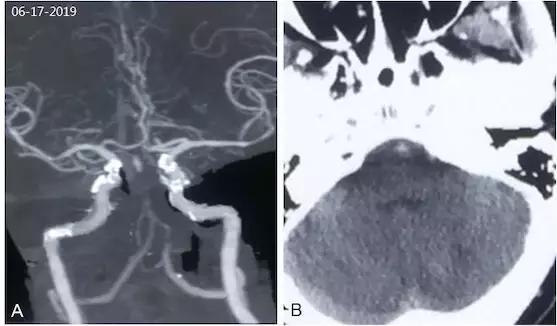

头颅MRI(2019-6-17): 小脑半球多发新近梗死灶(图1)。

图1

颅内CTA(2019-06-17):基底动脉未显影,左椎动脉V4段狭窄(图2A)。头颅CT(2019-06-17):小脑半球多发梗死(图2B)。

图2